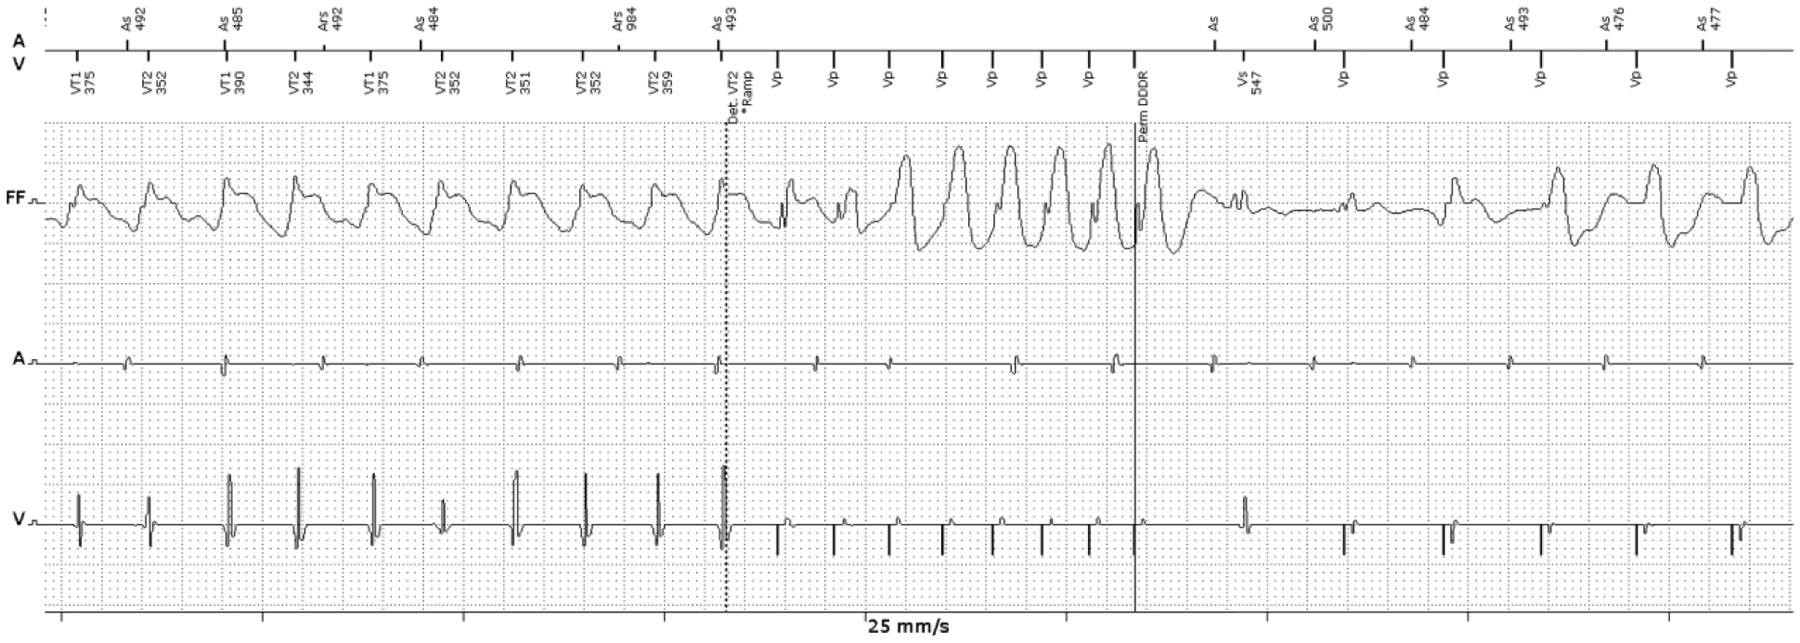

We present a recent example of a young patient with a history of Lamin A/C mutation cardiomyopathy who recently was referred to our center with VT storm. He had multiple VT episodes and most of them were successfully terminated with ATP therapy (Figure 1). Coronary angiography showed no obstructive coronary disease. He underwent VT mapping and ablation. Bipolar and unipolar mapping showed peri-aortic and mitral low voltage as a surrogate for scar (Figure 2 A). Constant and progressive fusion confirmed a re-entrant VT mechanism (Figure 2 B), and entrainment and activation mapping localized the VT to the basal anteroseptal LV at the borderzone of the scar region. This arrhythmia was easily pace-terminated with burst pacing at 75% tachycardia cycle length from the RV apex (Figure 2 C). This case illustrates a scar-based monomorphic VT that is commonly seen with NICM and demonstrates the ability of these arrhythmias to be pace-terminated with ATP.

Figure 1.

Example of a monomorphic VT terminated by ATP in a patient with non-ischemic cardiomyopathy. This patient has a history of non-ischemic, Lamin A/C mutation cardiomyopathy. Intracardiac ICD electrogram of the episode shows monomorphic VT (162 bpm) terminated with 1 round of burst ATP.

(VT: ventricular tachycardia, ICD: implantable cardioverter-defibrillator, ATP: anti-tachycardia pacing)